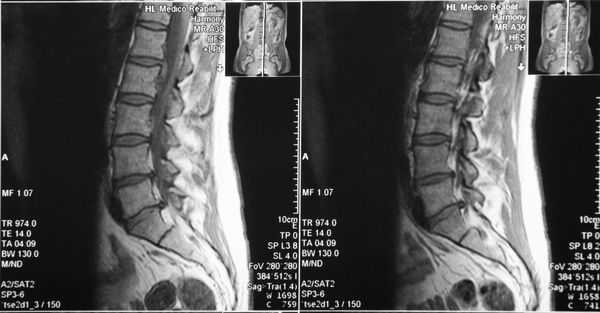

Магнитно-резонансная томография (МРТ) позволяет оценить состояние головного мозга, наличие свежих и старых ишемических очагов. В режиме МРТ ангиографии возможно без контраста оценить состояние шейных и внутримозговых отделов позвоночных артерий. С точки зрения визуализации артериальной патологии МРА уступает компьютерной томографии с ангиографией, однако не требует использовани контрастного вещества, что важно для пациентов с нарушением функции почек. На представленном изображении показана тромботическая закупорка левой позвоночной артерии (отсутствие контрастирование показано стрелкой).